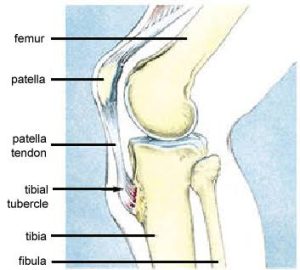

Anatomy

The knee has two growth plates which are active bone regeneration that stay open until children have stopped growing. There is one on the lower part of the thigh bone and one on the top of the shin bone.

When the body has a sudden growth spurt there is lots of activity as the growth plates are laying down a lot more bone cells. Then when the tendons around the knee start pulling on this bone, it causes some irritation and inflammation. This occurs right at the front of the knee at the top of the shin bone where the tendon from the thigh muscles attaches below the kneecap. It becomes inflamed and sore.